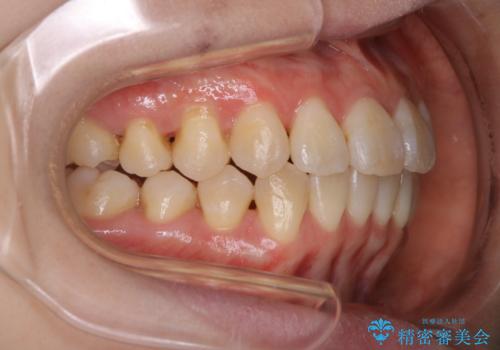

- 前歯のがたつきが気になるとご相談にいらした方です。右側前歯部のクロスバイトの他、左側にもシザーズバイトが認められたため、インビザラインにて治療を行いました。出産直後のため、ご自身の時間がなかなか取れないとの事で、最小限の来院回数で治療を勧められるように計画しました。

患者様ご自身で使用時間をしっかり管理して頂くことを条件に、最低限の来院回数で治療を進めていきました。20時間以上の使用を厳守して頂けたことで、少ない来院回数にて治療を終了することが出来ました。前よりも噛みやすくなったと大変喜んでいただけました。